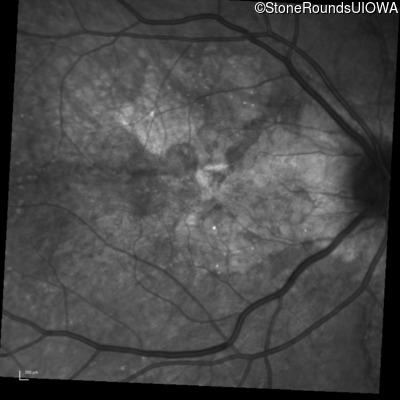

Infrared Fundus Photograph - Right - 20/20 -1

Exemplar

Infrared Fundus Photograph - Left - 20/20 -2